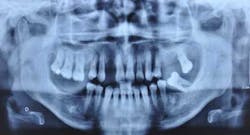

The author reviews a case study involving a 40-year-old female whose treatment included multiple prosthetic procedures.